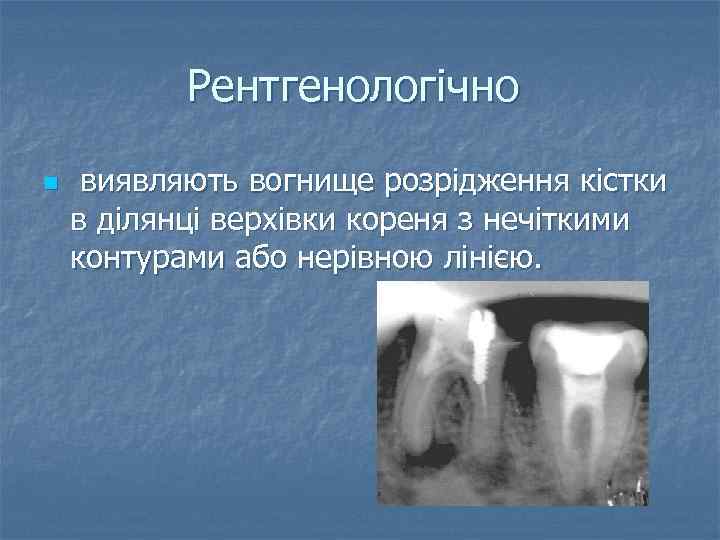

Рентгенологічно n виявляють вогнище розрідження кістки в ділянці верхівки кореня з нечіткими контурами або нерівною лінією.

Рентгенологічно n виявляють вогнище розрідження кістки в ділянці верхівки кореня з нечіткими контурами або нерівною лінією.